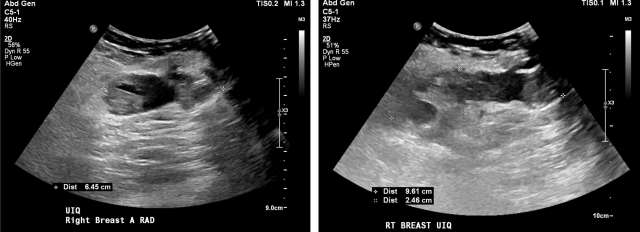

• US: Complicated hypoechoic or isoechoic fluid collection. Mobile debris within the fluid collection and hypervascularity of the adjacent breast tissue are characteristic, Figure 1.7

Case: Post-Surgical Fluid Collections Figure 1

Figure 1 - Ultrasound demonstrates septated, heterogenous fluid collection with surrounding hypervascularity. The patient was 3 weeks status post mastectomy and presented with breast redness and tenderness. The collection was drained, with cultures growing staph aureus.

• US: Heterogenous fluid collection with fluid-fluid level, Figure 2.

Case: Post-Surgical Fluid Collections Figure 2

Figure 2 - Ultrasound demonstrating post-surgical hematoma of the right breast. Heterogenous fluid collection with fluid-fluid level (yellow arrow). There was ecchymosis overlying the area of interest in the upper inner quadrant.

• US:  Anechoic simple fluid collections. Complicated fluid collections with heterogenous echogenicity are also possible, Figure 4.17

Case: Post-Surgical Fluid Collections Figure 4

Figure 4 - Homogenous hypoechoic fluid collection with internal debris, compatible with seroma. Smooth, well circumscribed walls without surrounding hypervascularity make abscess less likely.